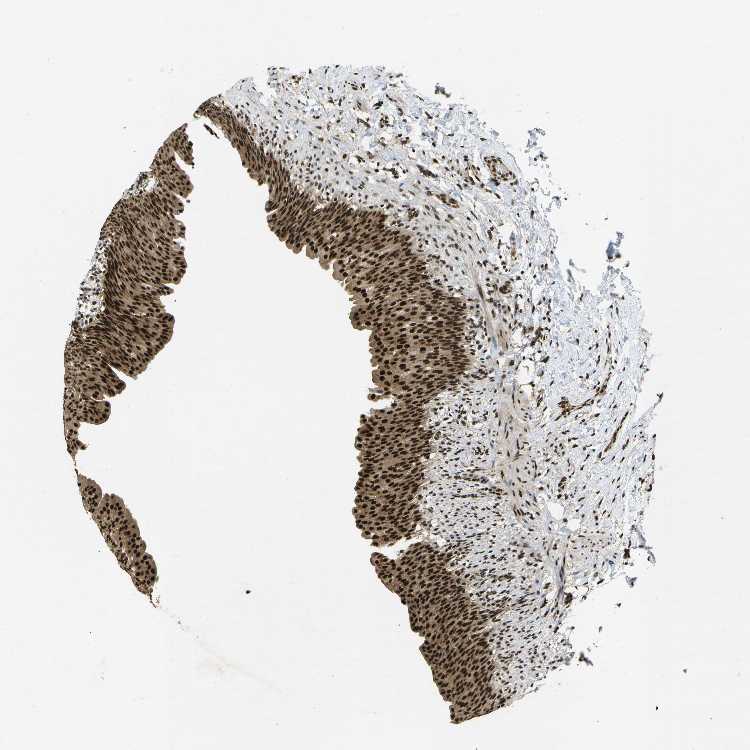

URINARY BLADDER - Antibody stainingi

Antibody staining in the annotated cell types in the current human tissue is reported as not detected, low, medium, or high, based on conventional immunohistochemistry profiling in selected tissues. This score is based on the combination of the staining intensity and fraction of stained cells.

Each image is clickable and will lead to virtual microscopy that enables deeper exploration of all samples and also displays staining intensity scores, fraction scores and subcellular localization as well as patient and tissue information for each sample.

Antibody HPA016949

Urothelial cells High